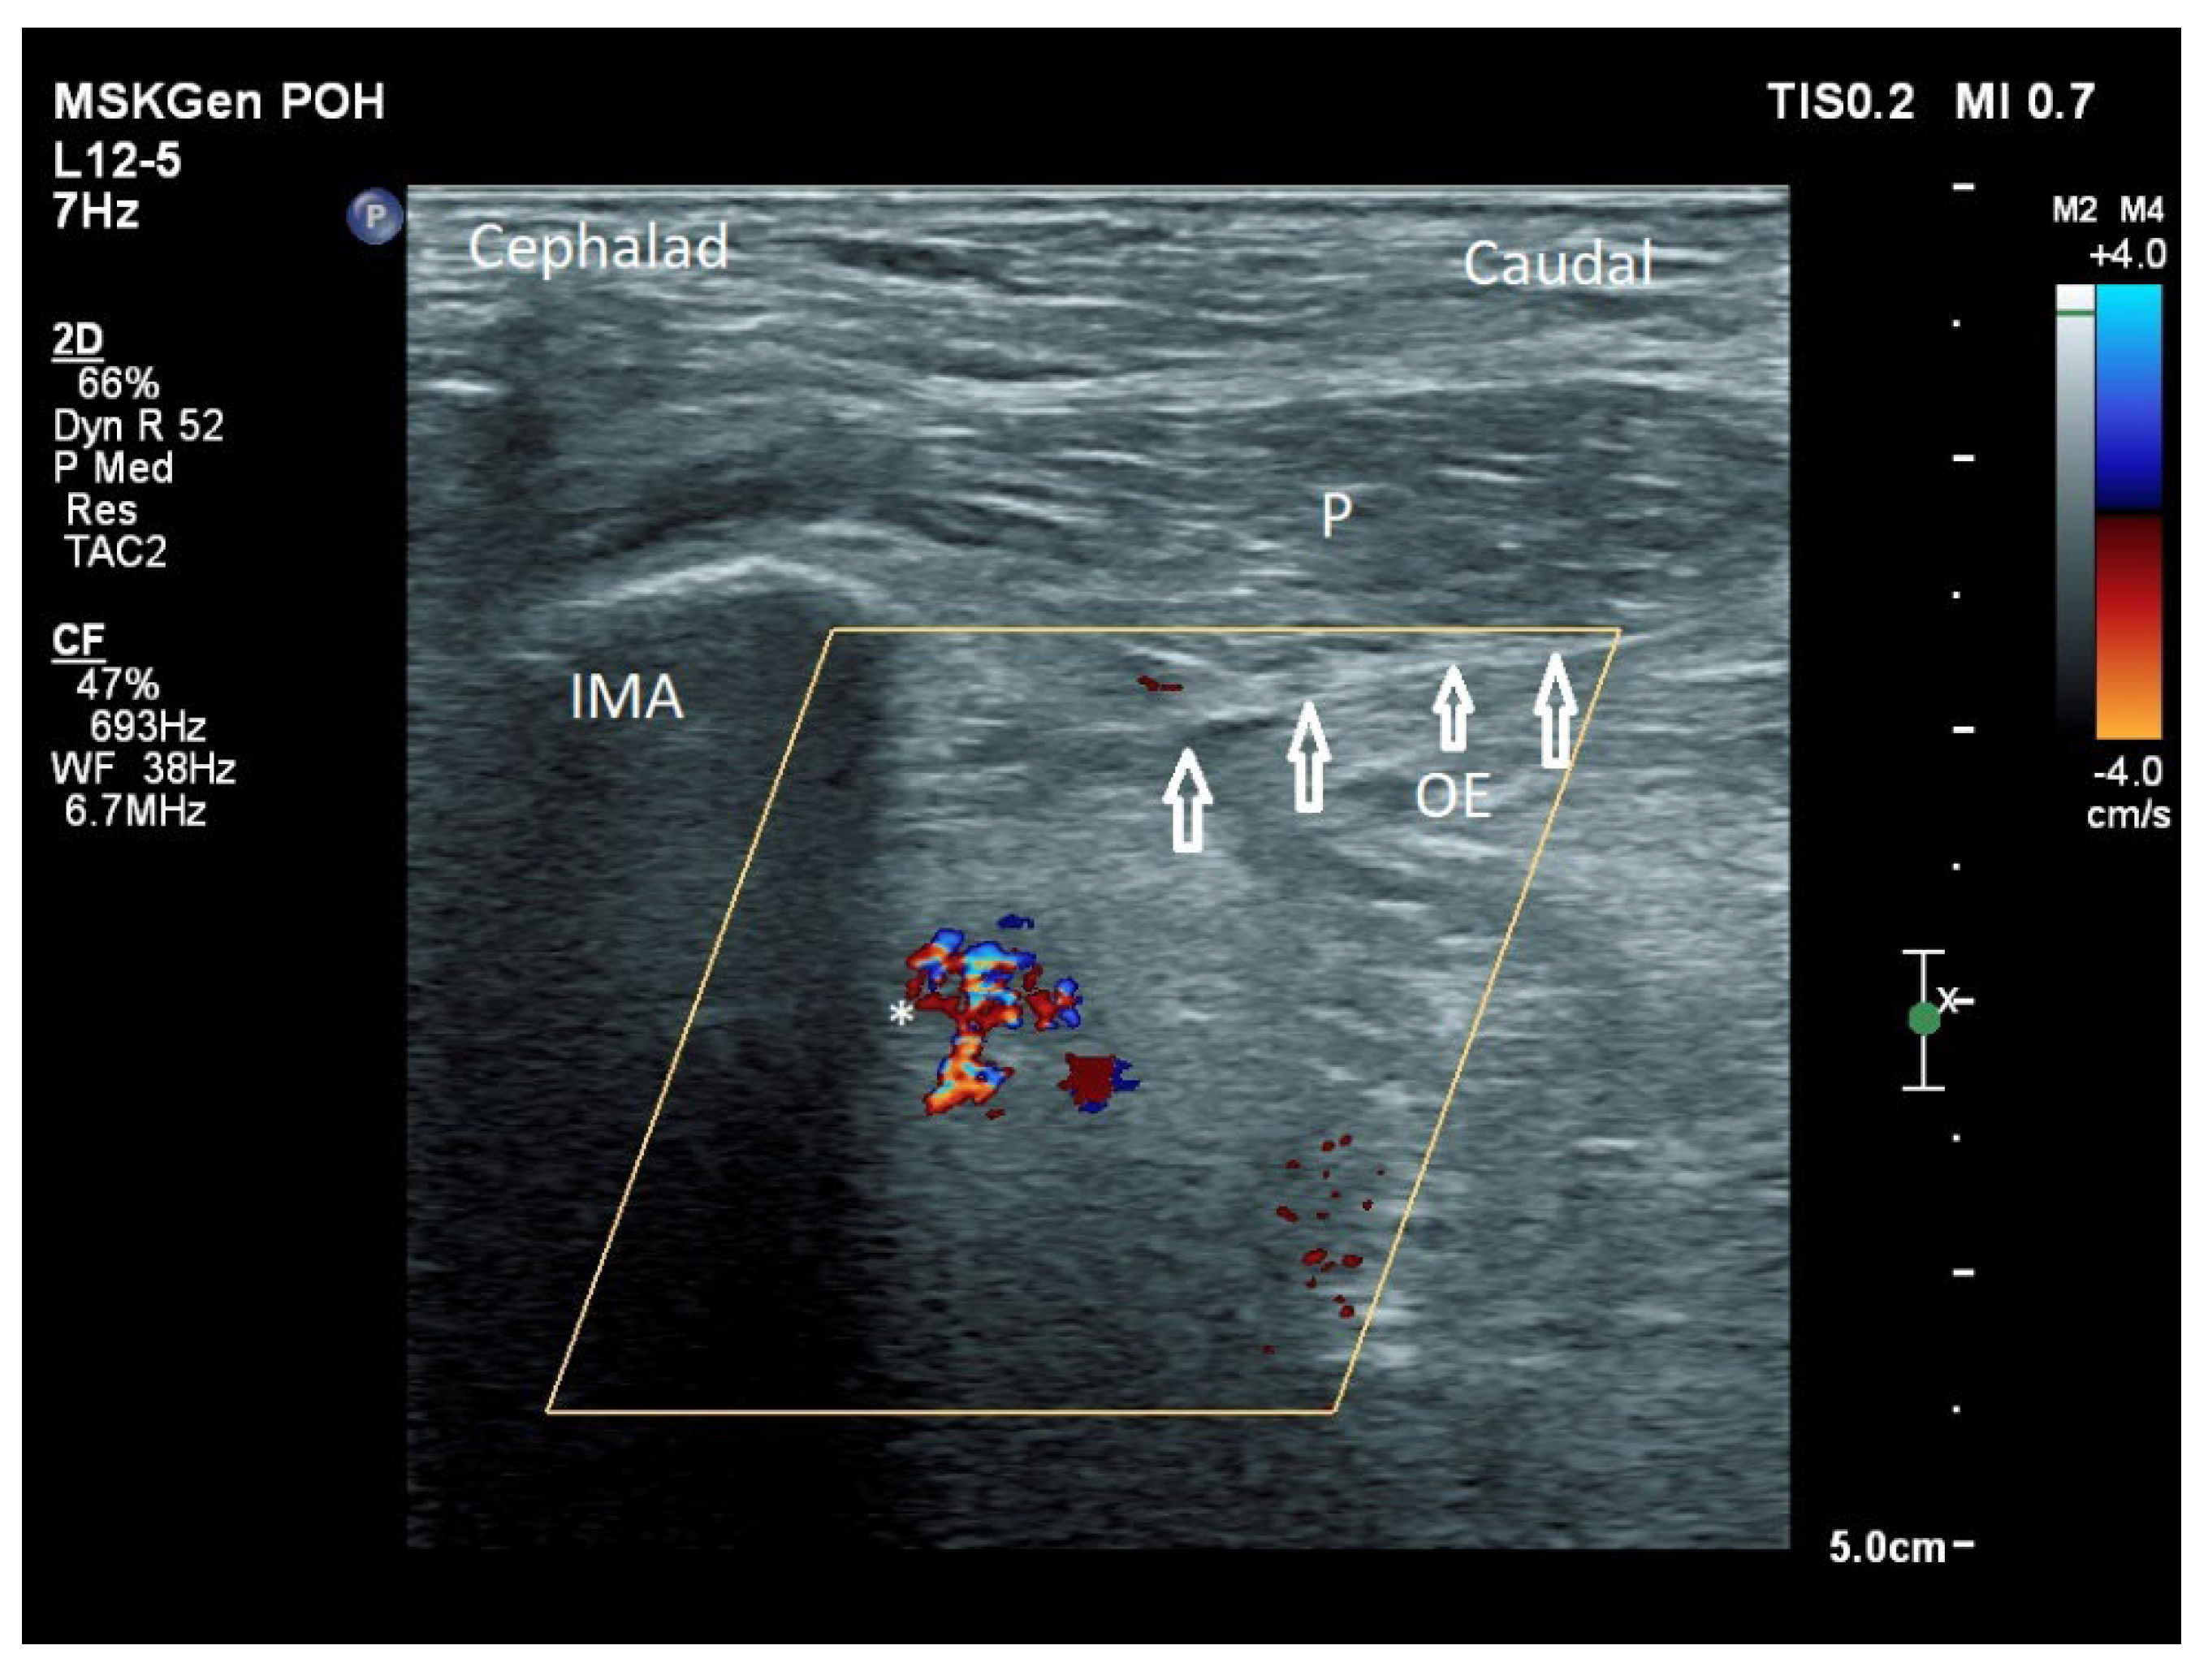

In addition to the classical PENG injection, our modified approach highlighted the addition of pericapsular infiltration in the iliopsoas plane to cover the low articular branch of the femoral nerve and a sagittal approach to target the ONAB. The algorithm was still used to perform diagnostic blocks, followed by alcohol neurolysis 10 min later for those with a positive diagnostic block in the same setting under real-time ultrasound guidance (Philips Affiniti 70, 5–12 MHz linear probe or 1–5 Hz curved probe depending on the depth of the target). In the modified approach, the procedure consisted of 3 needle insertions with the use of 22-gauge 10 cm Quincke needles. The first needle for the high femoral nerve articular branches (high FNAB branches) and AON was inserted in the same way as the PENG approach between the anterior inferior iliac spine (AIIS) and the iliopubic eminence (IPE) deep to the psoas tendon (Figure 2 and Figure 3). A second needle for the low branches of FNAB was inserted in-plane from lateral to medial and advanced through the sartorius, rectus femoris and iliopsoas muscles. The final needle position was in the plane superficial to the iliofemoral ligament medial to the rectus femoris tendon over the femoral head (Figure 4 and Figure 5). The third injection for the obturator nerve articular branches was used to target the caudal aspect of the inferomedial acetabulum (IMA) by scanning in a sagittal plane with a caudal-to-cephalad needle trajectory. The precise localization of the caudal aspect of the IMA could be first approached via the ordinary way (an oblique scan) as described in our first case series [5]. The probe was slowly rotated obliquely until the acetabulum, femoral head, and neck were aligned in the same plane, with the superomedial acetabulum coming into view. The probe was then slid caudally with the end point being the presence of the acetabulum without the femoral head. This referred to the location of the inferomedial acetabulum. The probe was then adjusted until the IMA was in the middle of the image, followed by rotating the probe by approximately 60 degrees (Figure 6). In this scan, the pectineus, the caudal aspect of the IMA and, occasionally, the obturator externus were seen. The ONAB could be visualized in the wedge of the subpectineal space directly adjacent to the IMA. Before any needle insertion, the probe was tilted slightly medially towards the obturator foramen to look for the acetabular/posterior branch of the obturator vessels which are usually deeper than the ONAB. The needle was then inserted from caudal to cephalad in-plane until the needle tip reached the wedge space consisting of the ONAB (Figure 7). In case the wedge space could not be clearly visualized, the needle tip would then be advanced until touching the caudal bony surface of the IMA directly underneath the pectineus. Then, 0.5–1% ropivacaine (4, 3 and 2 mL, respectively) was injected into the above three landmarks. The needles were left in situ during the diagnostic test while their positions were reconfirmed by ultrasound before 100% alcohol was injected into the above targets with volumes in a 1:1 ratio between alcohol and local anaesthetics. A decrease of ≥50% in composite pain score on hip flexion at 45 degrees 10 min after the blocks signified a positive diagnostic block. As a post-neurolysis routine manner, stylets were reinserted before needle withdrawal.

Our modified approach to the ONAB would have the following advantages over the ordinary oblique approach published in our first case series [5]. First, in patients with hip fracture, their fractured limb is commonly externally rotated. This would deviate the femoral vessels to overlay the needle trajectory to the ONAB at the inferomedial acetabulum (Figure 8). This sagittal approach can reliably avoid the femoral vessels in the trajectory. Second, the sagittal scan allows us to visualize the acetabular/posterior branch of the obturator vessels underneath the ONAB, and this can minimize the chance of inadvertent puncture of these small vessels. Third, the ONAB anatomically courses along the caudal aspect of IMA instead of the lateral aspect of IMA [24]. The modified approach can potentially target the ONAB more precisely. Lastly, the modified approach allows the ONAB to be visualized clearly in non-obese patients, whereas the ordinary approach only relies on a rough bony landmark of IMA. Although a large volume of subpectineal injection may lead to a spread to the motor branch of obturator nerve [27], we did not identify any case with neurological deficit along the obturator nerve distribution in our study.

Figure 7. Approaching the ONAB in a sagittal plane from a caudal to cephalic direction. IMA: inferomedial acetabulum, P: pectineus, OE: obturator externus, *: acetabular and/or posterior branch of the obturator artery, white hollow arrow: needle.